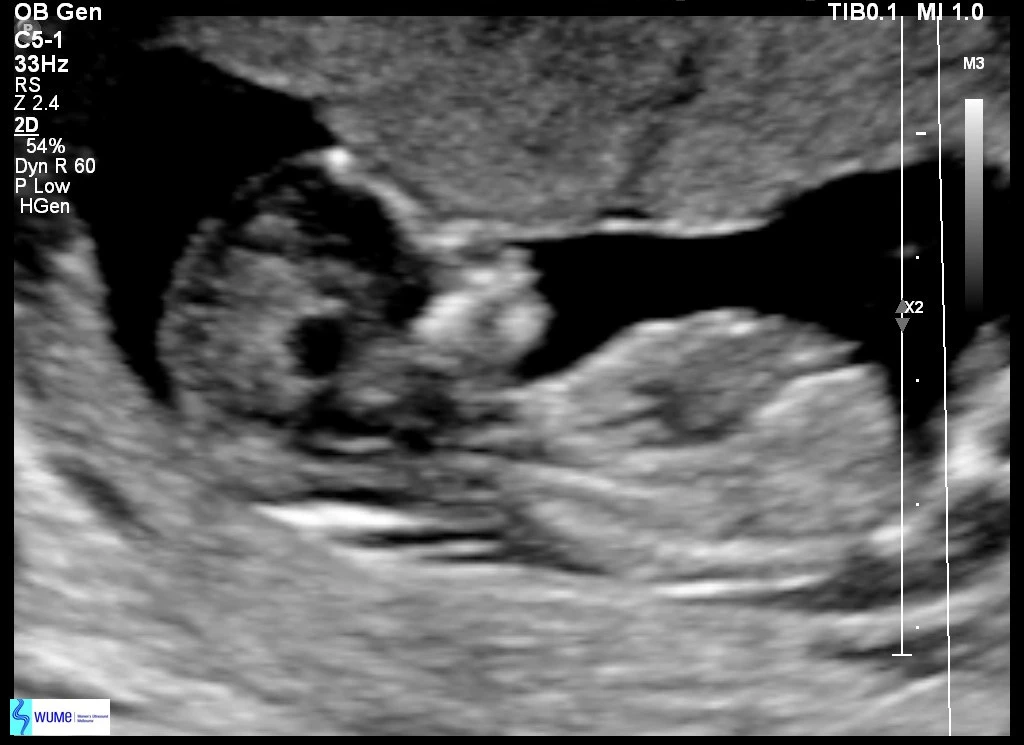

13주 2일

너에게 쓰는 편지가 이제 정말 너라고 부를 수 있는 네가 나에게 왔구나 싶다. 오늘 긴 팔다리와 손가락 발가락까지 있는 너를 보고 왔어. 다행히 시아버님의 코를 닮지 않은 오뚝한 코까지 보여 얼마나 안심했는지 몰라. 심장소리도 너무 크고 움직임도 너무 좋고 다 너무 좋았어. 초음파를 보러 가기 전 불안한 마음은 어쩔 수 없나 봐. 건강한 너를 보니 마음이 노여 병원을 다니오니 긴장이 풀리더라.